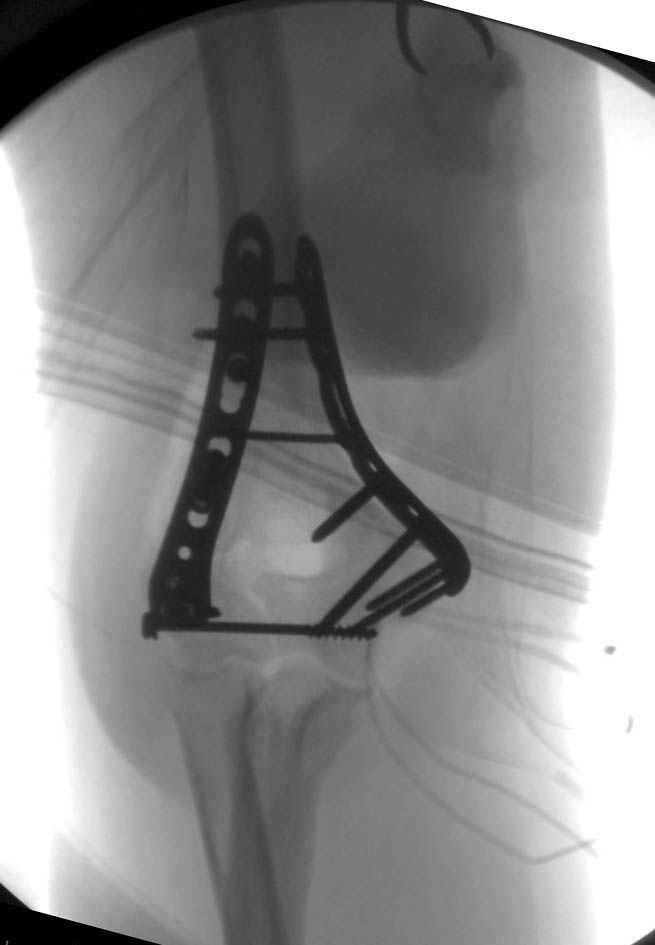

Солидарен с мнением обоих Александров (Челнокова и Рыкова): точную репозицию такого перелома вряд ли удастся выполнить закрыто. Даже во время открытого вмешательства это сделать непросто. Неслучайно предложен костно-пластический доступ с временным отсечением локтевого отростка. И по методу фиксации согласен с Александром Челноковым: 2 пластины. В качестве примера привожу рентгенограммы одного из наших пациентов с аналогичным повреждением.

С уважением, А. Золотов, Приморский край.